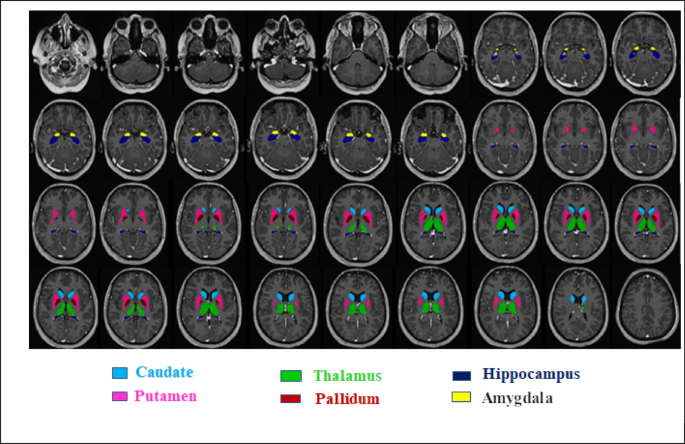

For the present study, the AssemblyNet segmentation pipeline was selected. AssemblyNet is a robust ensemble of convolutional neural networks developed for 3D whole-brain segmentation. Volumetric measures were extracted for both global and regional brain structures. These included white matter, grey matter, Cerebellum white matter, and Cerebellum grey matter. Additionally, subcortical nuclei (Amygdala, Caudate, Hippocampus, Pallidum, Putamen, and Thalamus), limbic cortex and cortical lobes (Frontal, Temporal, Parietal, and Occipital) were quantified (Fig. 2)33.